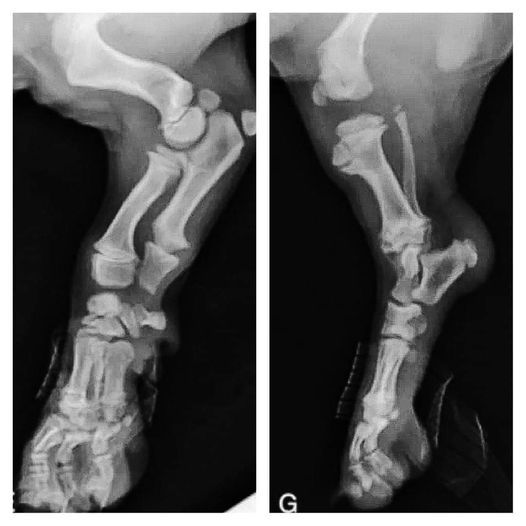

Lorsque vous accueillez votre chiot entre 8 et 12 semaines, ayez ces images à l'esprit, ses os ne touchent pas encore. S’il se déplace si maladroitement avec ses grosses pattes et ses mouvements bancals c’est parce que ses articulations sont entièrement constituées de muscles, de tendons, de ligaments, son squelette n’est « pas soudé ».

Photos Veteriankey.com @ 62 jours

L'ossification endochondrale (le processus durant lequel le cartilage se transforme en os), diffère selon la taille adulte du chiot. L’ossification complète avec fermeture des plaques de croissance se produit entre 3 mois dans les races de mini et 24 mois dans les grandes races (voir photos) ...